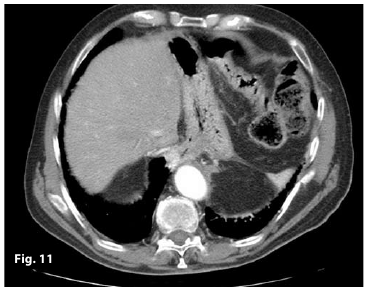

Figure11